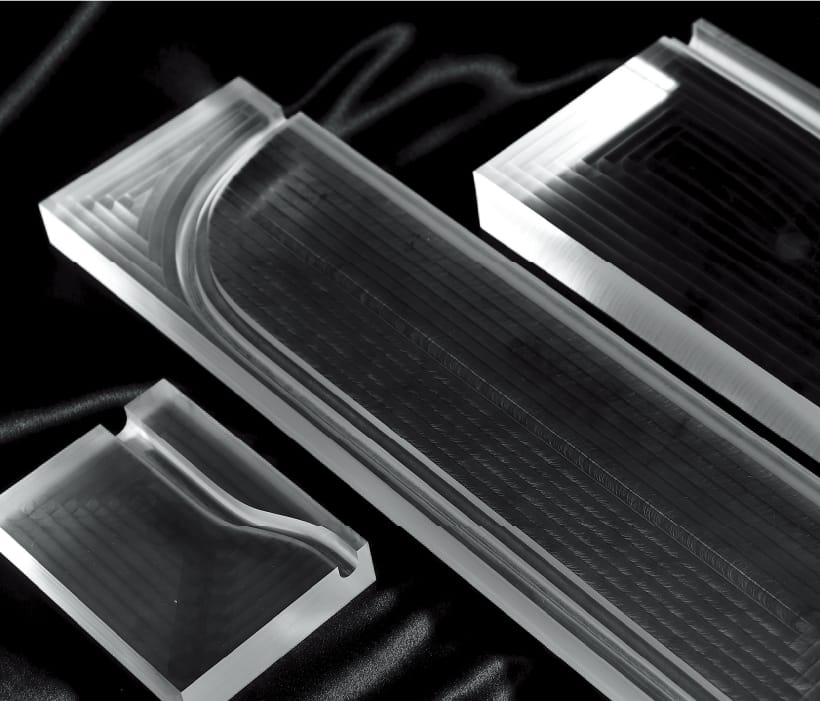

JMC's medical model fabrication service uses 3D printers and other digital technologies to achieve a high degree of freedom in model fabrication. 3D printed resin models are combined with vacuum casting technology to transfer the shape onto transparent, soft, and other materials. By combining 3D printed resin models with vacuum casting technology, we are able to transfer shapes onto transparent, soft, and other materials, providing services that thoroughly pursue the shapes, textures, and functions that customers demand.

Rigid model with short delivery time

We have a system in place that allows us to work 24 hours a day, 7 days a week on rigid models that are output directly from the 3D printer, so that we can deliver them quickly to our customers in fields that require speed, such as preoperative simulation and prototyping of medical devices. We have a variety of output methods, including optical, SLS, and inkjet, so you can choose the most suitable method for your application.

rapid prototyping (machine)

Complex shapes can be integrally molded in a short time. Since the liquid resin is cured by the laser one layer at a time, the "corner radius" (radius of a cylindrical tool) that occurs in blade processing is not generated.

This makes it possible to reproduce the microscopic shape of organs.

Cutting materials

Materials such as acrylic, ABS, polycarbonate, and polypropylene can be used.